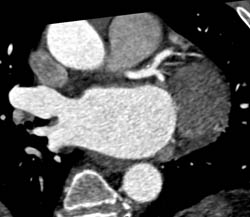

Aneurysm of Circumflex Coronary Artery